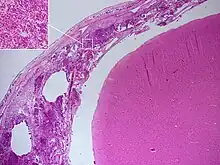

Autopsie

Le diagnostic de méningite peut être porté après la mort lorsqu'une autopsie est réalisée, montrant une inflammation de la pie mère et de l'arachnoïde avec des neutrophiles pouvant gagner le système nerveux central via les nerfs ou les vaisseaux méningés, parfois entourés de pus[36].